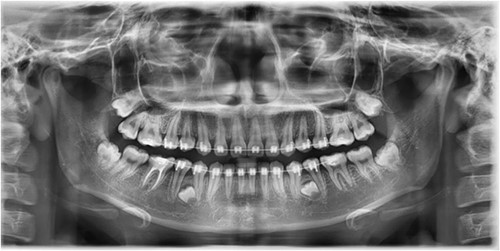

A Neumann full-thickness buccal flap was utilized to remove these during the course of orthodontic treatment. The shortcoming of the buccal surgical removal approach is that although it is better for visualization, it poses a high risk of trauma to the adjacent teeth or nerves [4, 5]. As the premolar was being removed on the right side, there was a fracture of the root apex (Fig. 2). On the left side, the premolar bud could be removed without any trauma to the adjacent tooth roots. After months of follow-up, there was normal bone formation, and no other symptoms were identified (Fig. 3).

Follow-up panoramic 1 week after removal of the supernumerary premolars.